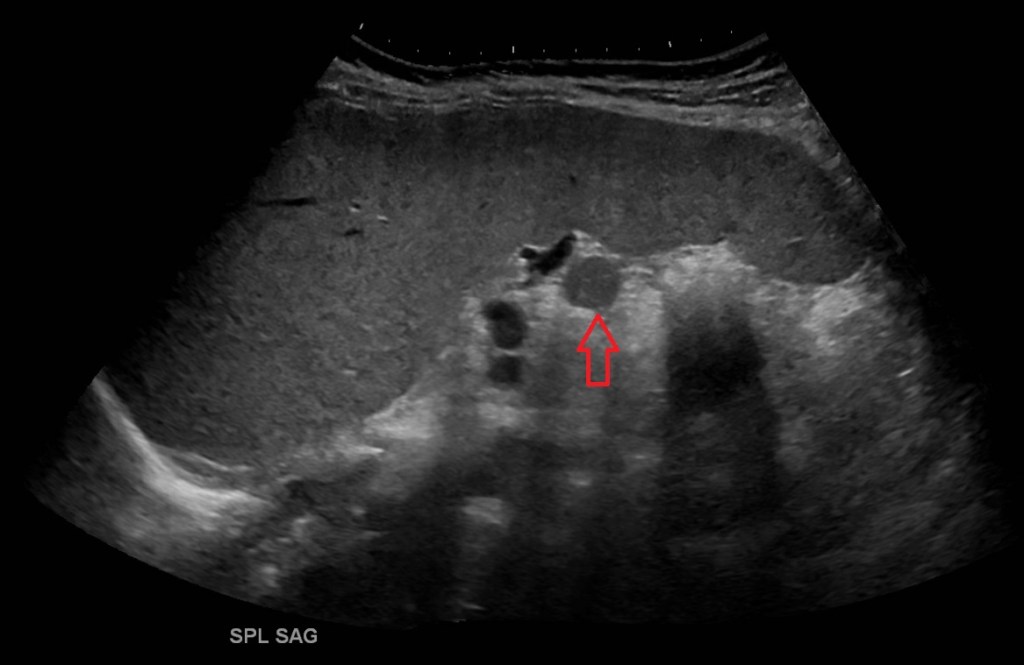

An accessory spleen is normal splenic tissue separate from the main mass of the spleen. Accessory spleens vary in size from a few millimeters to several centimeters, they occur most frequently near or at the splenic hilum. They are also quite common found in up to 16% of CTs of the abdomen and up to 30% of autopsies [1]. For the uninitiated the splenule may be mistaken for a tumorso it is important that the sonographer is aware of this variant. Splenunculi also occur post splenectomy, and may enlarge, although they usually retain a spherical shape. [2]

The most common location to find a splenule is by the splenic hilum however they have been documented in other parts of the body as close as the stomach and pancreas and as far as the scrotum. [3,4]